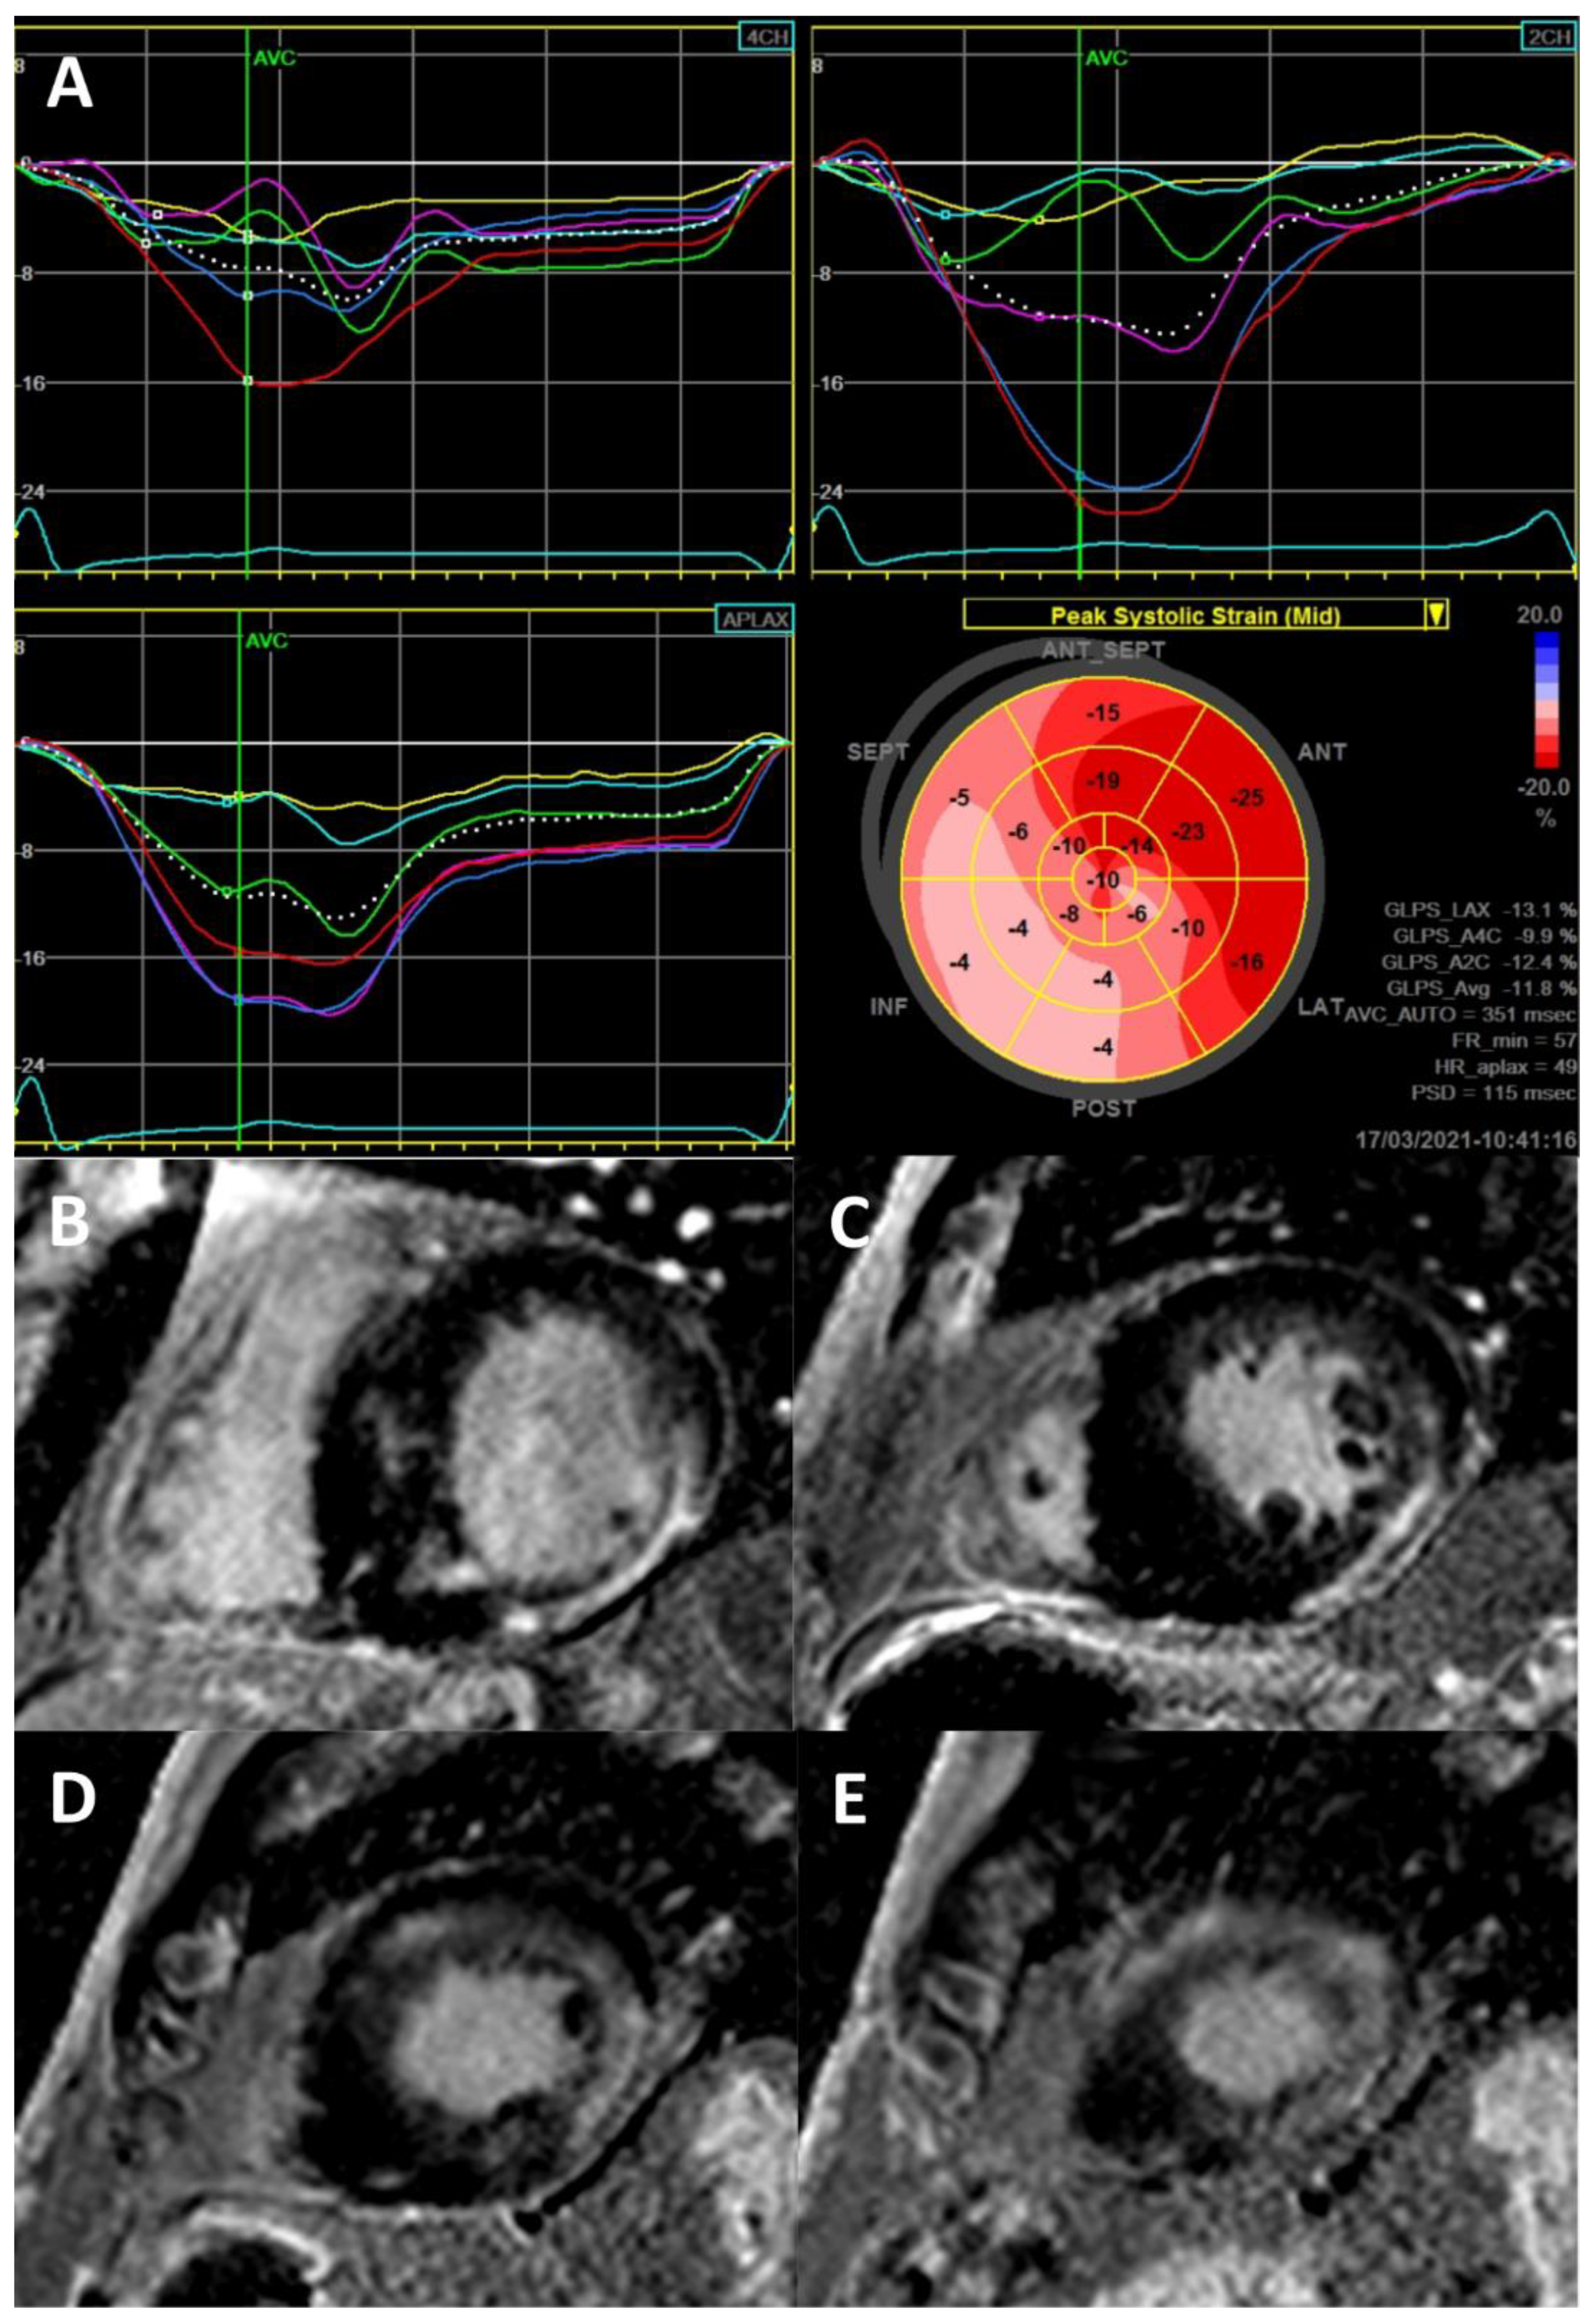

- Krämer, J.; Niemann, M.; Liu, D.; Hu, K.; Machann, W.; Beer, M.; Wanner, C.; Ertl, G.; Weidemann, F. Two-dimensional speckle tracking as a non-invasive tool for identification of myocardial fibrosis in Fabry disease. Eur. Heart J. 2013, 34, 1587–1596. [Google Scholar] [CrossRef] [Green Version]

- Vijapurapu, R.; Nordin, S.; Baig, S.; Liu, B.; Rosmini, S.; Augusto, J.; Tchan, M.; A Hughes, D.; Geberhiwot, T.; Moon, J.C.; et al. Global longitudinal strain, myocardial storage and hypertrophy in Fabry disease. Heart 2018, 105, 470–476. [Google Scholar] [CrossRef]

- Saccheri, M.C.; Cianciulli, T.F.; Lax, J.A.; Gagliardi, J.A.; Cáceres, G.L.; Quarin, A.E.; Kisinovsky, I.; Rozenfeld, P.A.; Reisin, R.C. Aadelfa Two-Dimensional Speckle Tracking Echocardiography for Early Detection of Myocardial Damage in Young Patients with Fabry Disease. Echocardiography 2013, 30. [Google Scholar] [CrossRef]

- Spinelli, L.; Giugliano, G.; Imbriaco, M.; Esposito, G.; Nappi, C.; Riccio, E.; Ponsiglione, A.; Pisani, A.; Cuocolo, A.; Trimarco, B. Left ventricular radial strain impairment precedes hypertrophy in Anderson–Fabry disease. Int. J. Cardiovasc. Imaging 2020, 36, 1465–1476. [Google Scholar] [CrossRef]

- Zada, M.; Lo, Q.; Boyd, A.C.; Bradley, S.; Devine, K.; Denaro, C.P.; Sadick, N.; Richards, D.A.; Tchan, M.C.; Thomas, L. Basal Segmental Longitudinal Strain: A Marker of Subclinical Myocardial Involvement in Anderson-Fabry Disease. J. Am. Soc. Echocardiogr. 2020, 24. [Google Scholar] [CrossRef]

- Shanks, M.; Thompson, R.B.; Paterson, I.D.; Putko, B.; Khan, A.; Chan, A.; Becher, H.; Oudit, G.Y. Systolic and Diastolic Function Assessment in Fabry Disease Patients Using Speckle-Tracking Imaging and Comparison with Conventional Echocardiographic Measurements. J. Am. Soc. Echocardiogr. 2013, 26, 1407–1414. [Google Scholar] [CrossRef] [PubMed]

- Cianciulli, T.F.; Saccheri, M.C.; Rísolo, M.A.; Lax, J.A.; Méndez, R.J.; Morita, L.A.; Beck, M.A.; Kazelián, L.R. Mechanical dispersion in Fabry disease assessed with speckle tracking echocardiography. Echocardiography 2020, 37, 293–301. [Google Scholar] [CrossRef] [PubMed]

- Réant, P.; Testet, E.; Reynaud, A.; Bourque, C.; Michaud, M.; Rooryck, C.; Goizet, C.; Lacombe, D.; De-Précigout, V.; Peyrou, J.; et al. Characterization of Fabry Disease cardiac involvement according to longitudinal strain, cardiometabolic exercise test, and T1 mapping. Int. J. Cardiovasc. Imaging 2020, 36, 1333–1342. [Google Scholar] [CrossRef] [PubMed]

- Gruner, C.; Verocai, F.; Carasso, S.; Vannan, M.A.; Jamorski, M.; Clarke, J.T.; Care, M.; Iwanochko, R.M.; Rakowski, H. Systolic Myocardial Mechanics in Patients with Anderson-Fabry Disease with and without Left Ventricular Hypertrophy and in Comparison to Nonobstructive Hypertrophic Cardiomyopathy. Echocardiography 2012, 29, 810–817. [Google Scholar] [CrossRef] [PubMed]